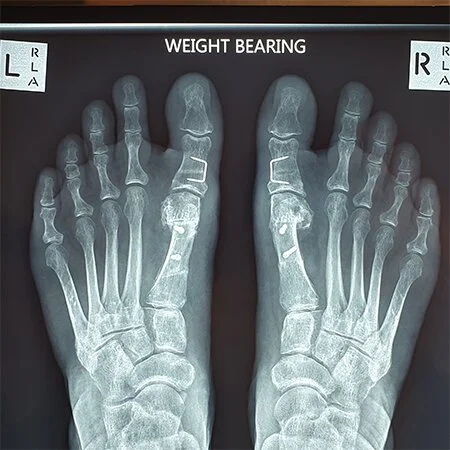

Post-operative X-ray of corrected bunions on both feet